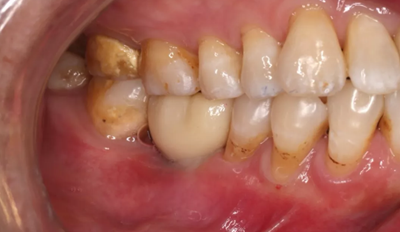

18、最終修復(fù)(口腔照片)

常規(guī)制作全瓷冠,試戴合適,粘接固位。

(攝于2018年6月13日)

修復(fù)完成6周隨診,牙齦形態(tài),色澤良好,咀嚼功能正常。

(攝于2018年7月27日)